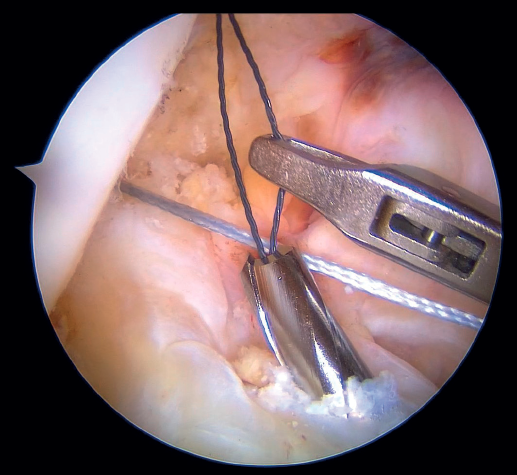

Our attention now turns to outside the knee, where the loop of the cortical suspension system (ACL Repair TightRope®) is secured to the ACL using the FiberRing® sutures. This device is a cortical suspension button with a loop of variable length, which also incorporates a high strength tape. To secure it, the suture marked as "1" on the card is first passed through the retriever thread of one of the FiberRing® sutures, and then the step is repeated through the retriever thread of the remaining FiberRing® suture. Next, this thread passing through the rings of the FiberRing® system is passed through the closed loop marked as "2". Finally, this thread is passed through the nitinol marked "3"; the card is held firmly and the nitinol is pulled so that the TightRope® thread passes through the cortical plate. At this point, part of the loop, the button and the threads connected to it (loop traction sutures, button lift sutures and high strength tape) remain outside the knee, waiting to be inserted into the joint (Figure 8).

The next step is to remove the femoral retriever thread through the cannula of the anteromedial portal, loading it with the traction and flipping sutures, but not with the high strength tape. By pulling on the retriever thread, the ACL RepairTightRope® sutures will pass through the femoral tunnel (Figure 9), exiting through the skin. Using the lift sutures, the button is then likewise advanced through the tunnel until it is flipped over the lateral femoral cortex (which can be checked by pulling firmly on the high strength tape, which still exits through the cannula). At this point, all that remains is to pull alternately on both loop traction sutures to shorten the loop and reduce the stump of the ACL until contact is made with its native footprint.